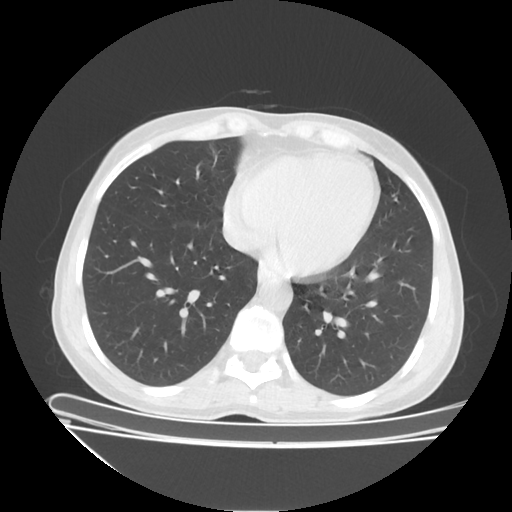

Generated VENOUS CT scan (A→B translation)

Full window (WL 1023.5, WW 4095 β†’ Low βˆ’1024, High +3071)

Lung window (WL -600, WW 1500 β†’ Low βˆ’1350, High +150)

Mediastinum window (WL 40, WW 400 β†’ Low βˆ’160, High +240)